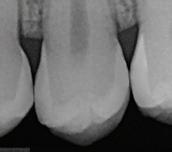

In the endodontic stage, conservative endodontic preparation and obturation with modern techniques are performed as they are for any tooth. All endodontic procedures are performed under an operating microscope to maximize visualization and illumination of the fracture line (Fig 1). The coronal portion of the newly placed gutta percha is removed 2 to 3 mm below the deepest extent of the crack in the affected canal to prepare for intraradicular barrier placement (Fig 2). Gutta percha is also removed 2 to 3 mm into the other noncracked canal orifices in the tooth to prepare for traditional orifice barriers. Microscopic transillumination with a fiber-optic light, in which an LED light probe is placed against buccal or lingual tissues overlying the roots, is utilized to illuminate the root and enhance visualization of the crack (Fig 3). A flowable resin-modified glassionomer or composite resin is then placed in this newly created void from the level of the gutta percha to the floor of the pulp chamber in all canal orifices (Fig 4). A composite resin core is then placed to permanently restore the endodontic access. If a temporary or permanent crown is not placed immediately after the endodontic procedures, the tooth is reduced

Periapical radiograph at the completion of the endodontic protocol. Resin-modified glass ionomer cement is placed as an intraradicular barrier in the distal canal, along the pulpal floor, and as an orifice barrier in the mesial canals.

The placement of intraradicular barriers in the described protocol is based on empirical data supporting their efficacy in improving both the seal and fracture resistance at the pericervical dentin. Studies on canal orifice barriers have noted that a minimum of 2 to 3 mm of material is necessary to create a coronal seal.28,29 In this protocol, removal of gutta percha to this depth was chosen to maximize the seal below the level of the crack on intact dentin. Studies have also shown that placement of these barriers can enhance the pericervical dentin’s

Fig 1. Microscopic visualization of the radicular extension of the crack (arrows) entering the canal.

Fig 2. Gutta percha removed 2 mm apical to the terminus of the fracture (arrows).